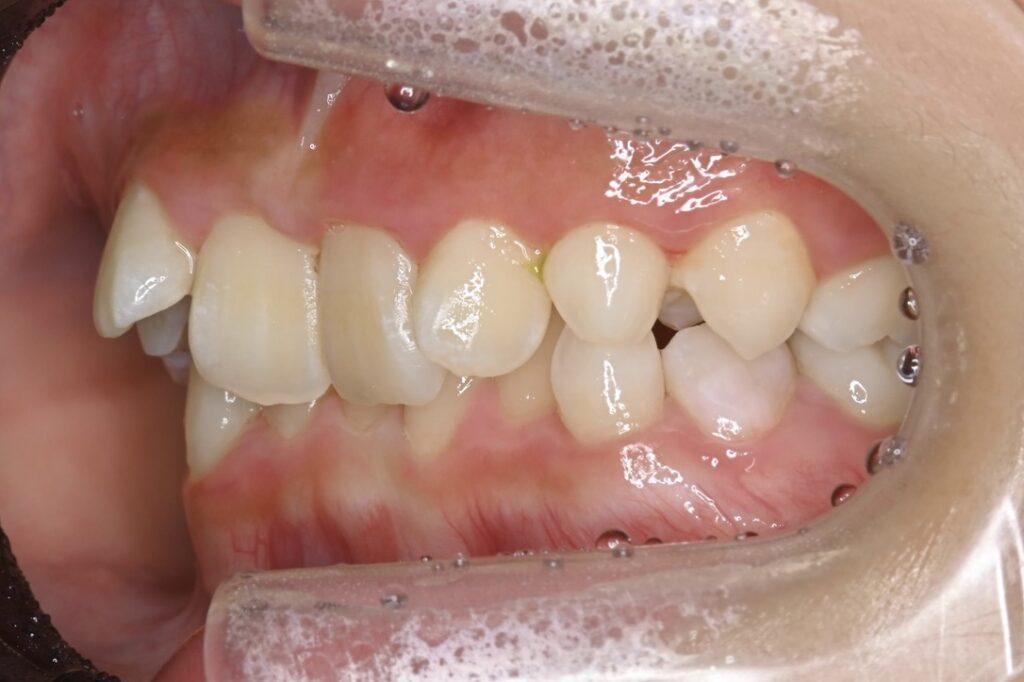

7歳 男児 小児矯正

BEFORE

主訴 通っている歯医者で矯正した方がいいと言われて気になっている。下の前歯がでこぼこしている。

診断名・主な症状 下顎前歯の叢生を伴う過蓋咬合

治療内容 上下の歯並びの幅を拡げつつ、前歯の関係を改善しました。